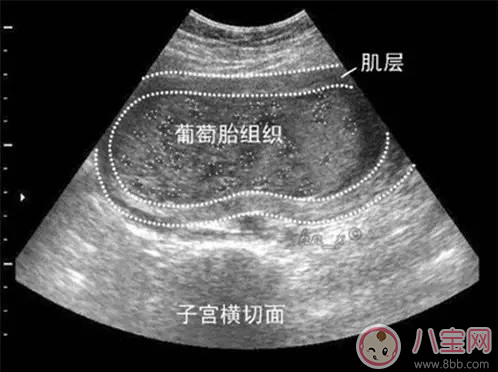

葡萄胎是由于絨毛膜滋養(yǎng)層細(xì)胞異常增生,絨毛發(fā)生水腫變形,呈無數(shù)個(gè)水泡相互連接,形似成串的葡萄,故名曰葡萄胎,又被稱為“水泡樣胎塊”?;加衅咸烟ヒ坏┐_診后要刮宮處理。如果子宮不大,內(nèi)容物比較少,那么一次就可以刮干凈,對(duì)女性子宮的傷害也較小,但是如果內(nèi)容物比較多,有數(shù)不清的水泡,會(huì)轉(zhuǎn)移,一次很難刮干凈,那么需要兩次刮宮。

懷上了葡萄胎的婦女在妊娠初期和大多數(shù)正常懷孕的婦女都是一樣的,可以表現(xiàn)有惡心嘔吐等早孕反應(yīng),但是隨著妊娠月份的增加,“孕婦”開始出現(xiàn)了一些與正常妊娠不同的表現(xiàn)。比如會(huì)出現(xiàn)腹部疼痛及陰道不規(guī)則流血等癥狀,早孕反應(yīng)也通常比普通的妊娠婦女表現(xiàn)得更劇烈、更嚴(yán)重,甚至持續(xù)的時(shí)間更長;還有的婦女懷上葡萄胎后,腹部異常的增大,肚子看起來要比正常孕周大得多,有的人甚至誤以為自己是懷上的雙胞胎或者多胞胎,殊不知卻是空歡喜一場。